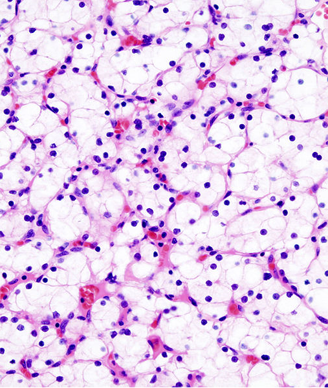

New research shows that tumors found in obese patients may be more indolent than those in nonobese patients, and this may, in part, be related to alterations in fatty acid metabolism explaining the obesity paradox in clear-cell renal cell carcinoma.